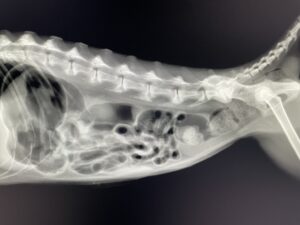

レントゲンがデジタルDRになりました!

今までフィルムが画像がきれいに撮れるということで、フィルムでの撮影を続けてきていたのですが、この度 デジタルのDRを導入することにしました。

DRは撮影からパソコンへ画像が映るまでにわずか5秒で出るという優れものであります。

画像も非常にきれいで 満足いく結果になっています。

獣医業界では最高クラスのピクセルサイズ(100μm 1500万画素)の細かさを誇る製品です。

より精度の高いレントゲン撮影が短時間でできるようになりました。

2025年10月3日 導入